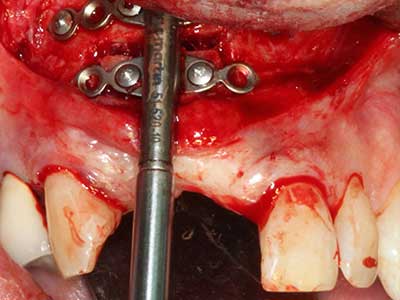

Sollen chirurgische Eingriffe mit unmittelbarer Knochenbeziehung an empfindlichen Strukturen wie Blutgefäßen oder Nerven erfolgen, so bergen rotierende Instrumente ein erhebliches Potential an iatrogener Schädigung. Gerade bei Nervdarstellungen nach iatrogener Schädigung, oder aber im Zuge einer Nervlateralisation für resektive und rekonstruktive Eingriffe oder Implantatinsertionen können piezoelektronische Geräte hilfreich sein Knochendeckel zu präparieren und nervnahe Hartgewebsanteile zu entfernen (Abb. 17-20). Ein leichter Kontakt des Nervstrangs zur Piezospitze bleibt dabei in der Regel folgenlos – allerdings kann eine unvorsichtige Vorgehensweise mit sägeartigen Bewegungen bzw. Ansätzen bei noch vorhandener knöcherner Unterlage durchaus temporäre oder aber auch permanente Nervschädigungen verursachen. Das Risiko einer solchen Schädigung wird jedoch als wesentliche geringer eingeschätzt als unter Anwendung von Säge- oder Fräsinstrumenten (Pereira, Gealh et al. 2014).

Wie sich in der Vergangenheit gezeigt hat stellt prinzipiell jeder knochenchirurgische Eingriff eine mögliche Indikation für die Piezochirurgie dar. So lässt sich die Präparation des mobilen Segmentes bei der Distraktionsosteogenese (Abb. 23-25) und der Sandwichosteotomie mit speziellen Ansätzen bewerkstelligen, ohne die für den Erfolg beider Techniken essenzielle Blutversorgung des krestalen Anteils zu gefährden (Gonzalez-Garcia, Diniz-Freitas et al. 2008).